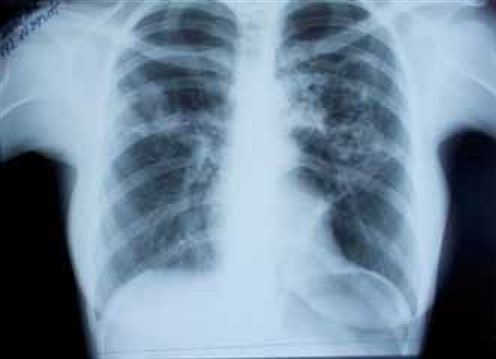

Заболела остро 14.09.15, когда появились описанные жалобы и повышение температуры до 39,6 °С. Лечилась самостоятельно (парацетамол, бромгексин) – без эффекта. Обратилась в поликлинику, где 17.09.15 выполнена обзорная рентгенография (РГ) органов грудной клетки (ОГК) (рис. 1)(О.В.Фатенков с соавт., 2018)

в верхних долях обоих легких – хлопьевидные участки неоднородной инфильтрации в S3 верхней доли с распадом и формированием полостей слева. Корни инфильтрированы. Диафрагма и синусы не изменены. Междолевая плевра слева подчеркнута.

На обзорной РГ ОГК при поступлении 25.09.15 (рис. 2) справа за I–III ребрами и слева за II–IV ребрами – участки неоднородной инфильтрации легочной ткани размерами 3 × 6 см справа и 6 × 8 см – слева, при этом слева нельзя исключить очаги деструкции в центре инфильтрата. Корни уплотнены, расширены. Сердце и аорта не изменены. Заключение: двусторонняя верхнедолевая полисегментарная пневмония с элементами деструкции слева. (О.В. Фатенков с соавт., 2018)